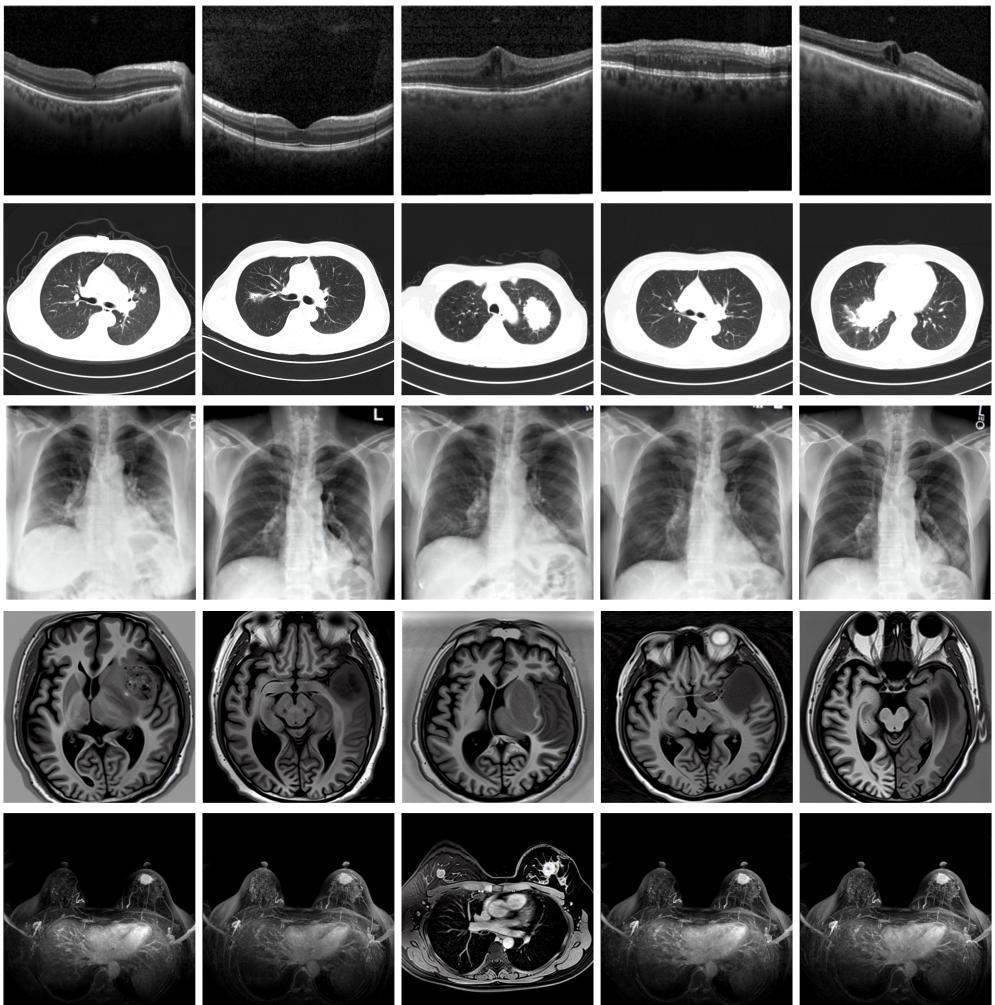

圖為由MINIM生成的高質(zhì)量醫(yī)學合成圖像(受訪者供圖)

“目前公開的醫(yī)學影像數(shù)據(jù)非常有限,我們建立的生成式模型有望解決訓練數(shù)據(jù)不夠的問題?!北本┐髮W未來技術學院助理研究員王勁卓說,研究團隊利用多種器官在CT、X光、磁共振等不同成像方式下的高質(zhì)量影像文本配對數(shù)據(jù)進行訓練,最終生成海量的醫(yī)學合成影像,其在圖像特征、細節(jié)呈現(xiàn)等多方面都與真實醫(yī)學圖像高度一致。

實驗結(jié)果顯示,MINIM生成的合成數(shù)據(jù)在醫(yī)生主觀評測指標和多項客觀檢驗標準方面達國際領先水平,在臨床應用中具有重要參考價值。在真實數(shù)據(jù)基礎上,使用20倍合成數(shù)據(jù)在眼科、胸科、腦科和乳腺科的多個醫(yī)學任務準確率平均可提升12%至17%。